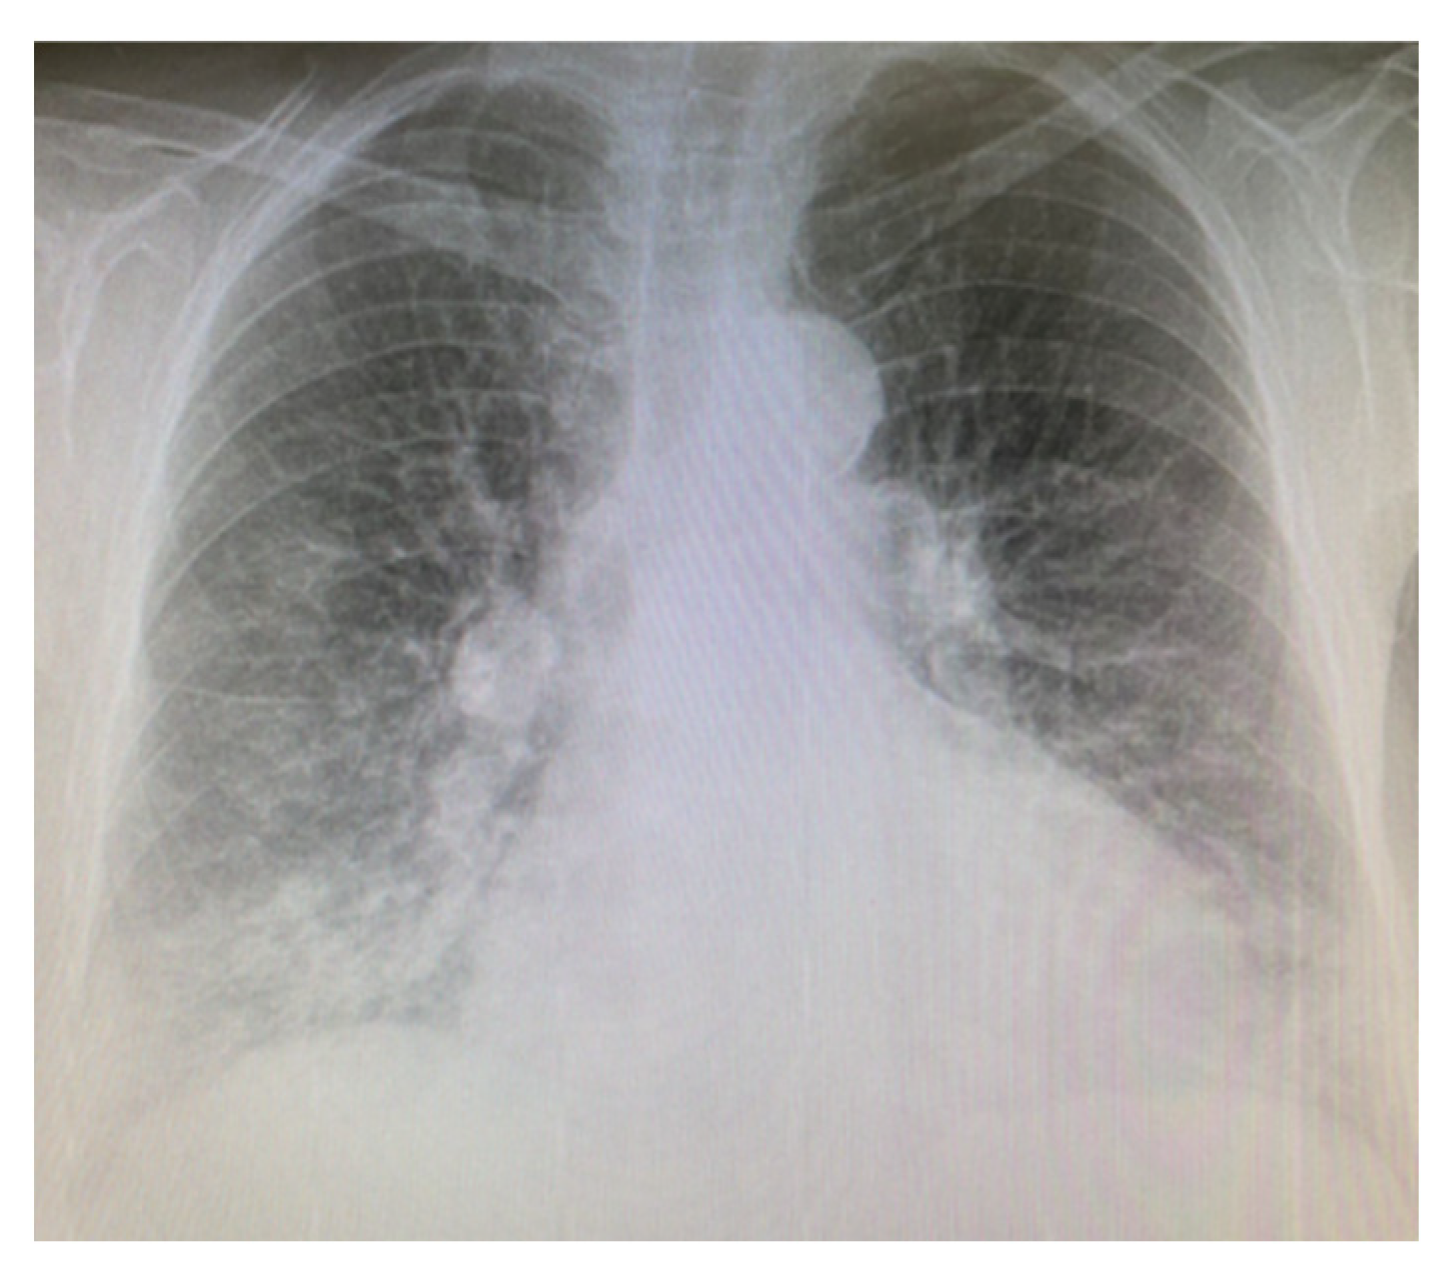

2.1. Case Presentation 1

2.2. Case Presentation 2

2.3. Case Presentation 3